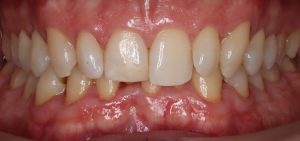

FULL

37 Semanas de tratamiento